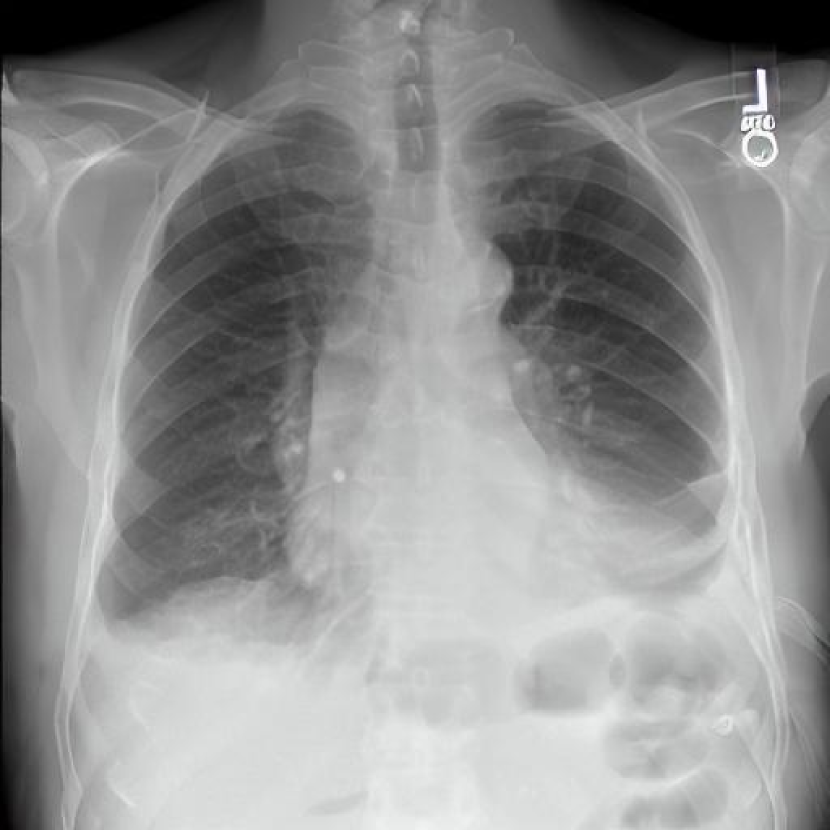

Leveraging Synthetic Data. With the advent of generative modelling tools, we are armed with the power to mitigate the problem of having a long-tail by supplementing the rare labels. We run a small experiment to evaluate whether we can use RoentGen [2], a prompt-based Stable Diffusion model to generate realistic chest X-rays and augment the training data. We generate about 5000 X-rays for training containing at least one pathology from the tail classes. We curate prompts for RoentGen by translating the Spanish reports available in the PadChest dataset to English, and also generate radiologist report-like prompts using ChatGPT 111chat.openai.com by providing curated templates. Figure 3 shows examples of prompts and the corresponding synthetic X-rays generated by RoentGen and verified by a radiologist.

Contribution of Synthetic Data. Figure 2 shows the increase in performance of the model over Table 1. This model was jointly finetuned on MIMIC CXR and a small synthetic dataset (refer Figure 3 for samples). Although the size of the synthetic dataset was too small for it to demonstrate an appreciable performance delta, these results show the promise of leveraging synthetic data to overcome the challenge of training on rare classes at least to some extent, especially since the biggest change is seen in the performance of the tail classes.